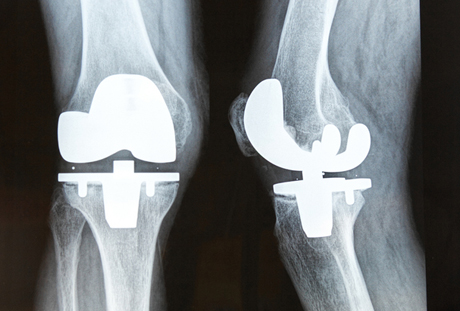

Il ginocchio è una delle articolazioni più complesse nel corpo umano. Esso deve sostenere il peso di tutto il corpo e deve sopportare impatti ripetuti dal fatto di camminare e correre. Al lavoro, deve sopportare i carichi più pesanti.

Il moserno intervento di sostituzione del ginocchio [destra] utilizza prodotti Hi-tech per mantenere la flessibilità e il peso-cuscinetto. Ma gli antichi non avevano questa tecnologia. Un cedimento del ginocchio significherebbe che il paziente sarebbe stato costretto al letto o su una sedia e probabilmente avrebbe dovuto sopportare un dolore grave se la connessione avesse subito uno spostamento. Il rimedio più efficace era quello di bloccare il giunto, come è stato fatto per Usermontu. Questo intervento avrebbe permesso al paziente di camminare con un bastone e avrebbe impedito il dolore continuo.